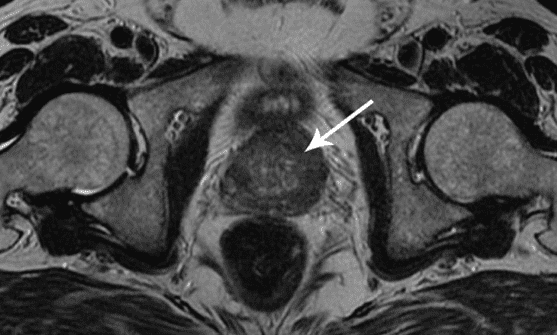

Rak prostate kod muškarca starog 58 godina. Uzročnik - dugotrajna apstinencija (od 51 godine). Pacijent je umro.